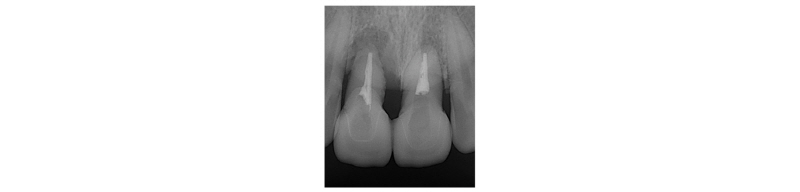

A 39-year-old male patient visited to the KyungHee University Dental Hospital with periapical abscess in the right maxillary central incisor. After clinical and radiographic examination, the tooth was planned to be extracted. The patient didn’t want to prepare the additional adjacent teeth. The right maxillary central incisor was planned to restore implant restoration and the left maxillary central incisor decided to proceed re-endodontic treatment and crown restoration (Fig. 1). Because of relatively young age of the patient, there was a lot of interest in esthetic results. Therefore, we planned to make provisional implant restoration and make a definitive prosthesis duplicating the emergence profile of the provisional restoration, and planned to use zirconia abutment when restoring the definitive prosthesis. First, preparation of maxillary left central incisor was done and maxillary right central incisor was extracted and cantilever provisional restoration was restored (Fig. 2, 3). Re-endodontic treatment of maxillary left central incisor was also progressed. After 3 months healing periods, implant placement was planned under evaluation of cone beam computed tomography scan with radiographic stent (Fig. 4). Implant placement was guided by surgical stent with bone graft (Bio-oss, Geistlich Pharma AG, Wolhusen, Switzerland) (Fig. 5, 6) and there were no systemic diseases would become problematic for implant surgery. Clinical and radiographic evaluation neither described any obvious active infection. Internal submerged type implant (4.0 mm×12.0 mm Implantium, Dentium, Korea) was placed and healing abutment was tightened. After surgery, provisional restoration was modified (Fig. 7). 3 months after implant surgery, fixture level impression was taken using pick-up impression coping (DPU 40 15 HL, Dentium, Korea) for provisional restoration (Fig. 8). Then, provisional crown with plastic provisional abutment (RAB 45 20 PHL, Dentium, Korea) was set for gingival molding (Fig. 9). During 3 weeks of provisional restoration period, the patient was satisfied with the function and the appearance of the provisional restoration. To transfer the emergence profile of provisional restoration, transfer technique was used with polyvinyl-siloxane impression material (Silagum, light body and putty, GmbH, Germany) (Fig. 10) and impression coping was modified. The final fixture level impression was taken using polyvinyl-siloxane impression material (Express light body and regular body, 3M ESPE, St Paul, MN, USA) after connection of modified pick-up impression coping (Fig. 11). A CAD/CAM zirconia abutment was milled and abutment adapted. Resin material (Pattern Resin LS; GC, America) and wooden sticks were used for delivery to laboratory of anterior teeth horizontal line. Midline also marked (Fig. 12). Splinted porcelain fused to zirconia prosthesis was fabricated. The root of the maxillary left central incisor being short and the prognosis being poor, so the crown was splinted with the maxillary right maxillary incisor implant prosthesis. The definitive crown and abutment were delivered to patient (Fig. 13). The esthetic, marginal fit was evaluated and the zirconia abutment was tightened to 30 Ncm using torque controller and splinted maxillary right and left definitive prostheses was set final cementation with resin-modified glass ionomer cement (FujiCEMTM, GC, Japan). Within the 3 years follow-up after treatment, the patient satisfied with the functional and esthetic outcomes, and the gingival architecture preserved that form.

Fig. 1. Pre-operative periapical radiograph on first visit. |